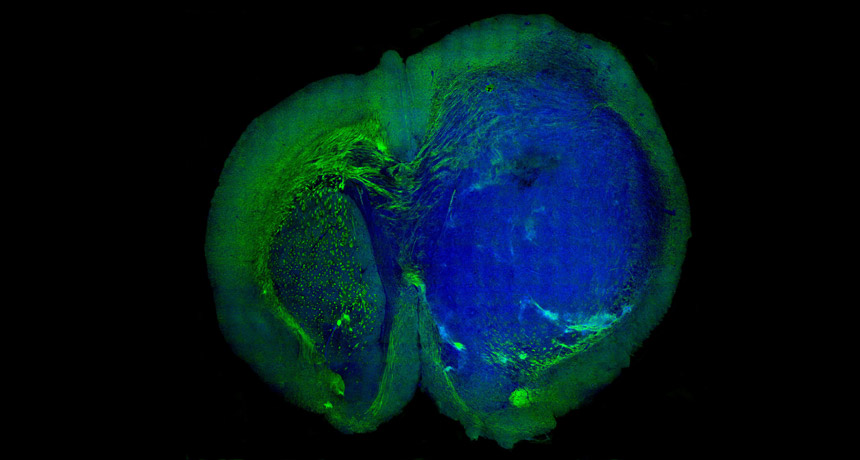

THE CUTTING EDGE A new technique generates colored images that differentiate tumor tissue (blue) in a mouse brain from surrounding healthy tissue (green). The technique may eventually improve brain surgery.

Ji et al/Science Translational Medicine